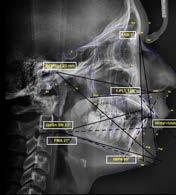

En la radiografía lateral de cráneo ( Figura 6 ) se ve la línea estética de Rickets, que el labio superior se encuentra a +0.5 mm y el inferior a -2 mm. En las mediciones cefalométricas más importantes en la figura 11 un ANB de 5º, GoGn-SN de 33º y FMA de 21º crecimiento normodivergente y Witts de -1 mm. A los criterios dentales encontramos

1-PLT de 129º e IMPA 99º proinclinación de incisivos tanto superiores como inferiores. En la radiografía panorámica (Figura 7), la presencia de 32 órganos dentarios, con terceros molares inferiores aún sin erupcionar y terceros molares superiores

Figura 6. Rx. cráneo lateral inicio progreso con trazos.

Secuencia de radiografías laterales de cráneo (Figura 15) vemos que el ANB disminuyo 1º de inicio a fin clase I con tendencia a clase II esquelética a final. Reducción de Witts 0.5 mm final, crecimiento normodivergente. Mandíbula más pequeña que el maxilar, cambio por el avance mandibular.

Referente a los criteriso dentales, el incisivo maxilar respecto a su base ósea tuvo una importante retroinclinación, inció en 129º y finalizó en 111º, en cuanto al incisivo inferior, este se proinclinó 1º, de 99º a 100º.